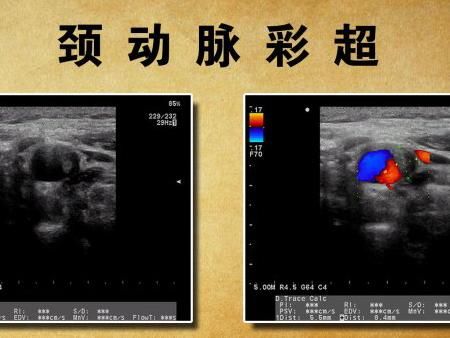

頸動(dòng)脈彩超

經(jīng)顱多普勒

??????? 我們?cè)诠?jié)目中介紹過(guò)兩種和血管相關(guān)的檢測(cè)方法,經(jīng)顱多普勒和頸動(dòng)脈彩超。有人有點(diǎn)糊涂了,這兩種不都是查血管是不是堵了嗎?有什么不同?經(jīng)顱多普勒觀察腦內(nèi)動(dòng)脈,頸動(dòng)脈彩超觀察頸部動(dòng)脈。這兩種檢查不能互相替代。